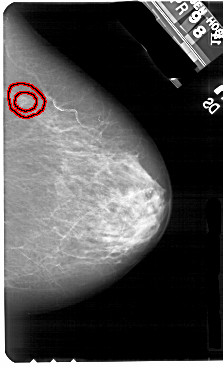

A_1700_1.RIGHT_MLO

RIGHT_MLO LINES 5491 PIXELS_PER_LINE 3331 BITS_PER_PIXEL 12 RESOLUTION 43.5 OVERLAY

FILE: A_1700_1.RIGHT_MLO.OVERLAY

TOTAL_ABNORMALITIES 1

ABNORMALITY 1

LESION_TYPE MASS SHAPE IRREGULAR MARGINS SPICULATED

ASSESSMENT 5

SUBTLETY 1

PATHOLOGY MALIGNANT

TOTAL_OUTLINES 1

BOUNDARY